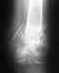

Если винты бессимптомные, не проникают в тазобедренный сустав - удаление не решит никаких проблем.